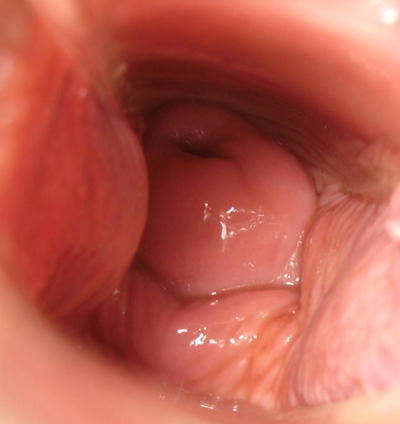

子宮頸癌圖片

宮頸癌

宮頸癌

宮頸癌

宮頸癌

宮頸癌

宮頸癌

宮頸癌

宮頸癌

宮頸癌

宮頸癌

宮頸癌

宮頸癌

宮頸癌

宮頸癌

宮頸癌

宮頸癌

宮頸癌

宮頸癌

宮頸癌

宮頸癌